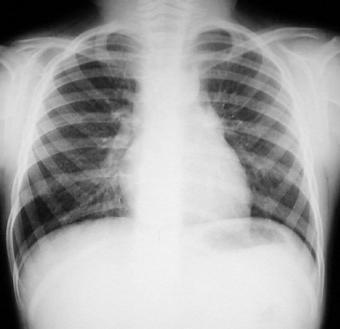

Radiografía del tórax

Rx. Tórax PA. Radio transparencia conservada en ambos campos pulmonares, sin infiltrados parenquimatosos, hileo y patrón de flujo pulmonar normal, senos costo y cardio-diafragmaticos libres, silueta cardiaca posición central normal, puede notarse el ensanchamiento del mediastino, por loe mas prominente en el lado derecho aspecto lobulado bien limitado, el esqueleto y partes blandas sin alteraciones.

Rx. Tórax LI. Radiopacidad peritraqueal redondeada y lobulada prominente en mediastino anterior y superior que incrementa el contraste de radiotrasperencia traqueal, observándose estenosis en su porción distal.